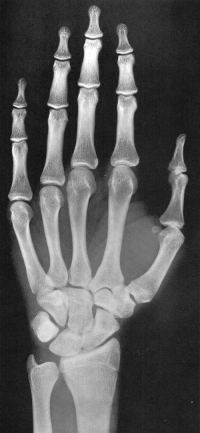

Sexo Masculino

14 anos

15 anos

Fonte: GREULICH, W.W. & PYLE, S.I.: Radiografic Atlas of Development of the Hand and Wrist. Stanford University Press, 2° edition, 1959.